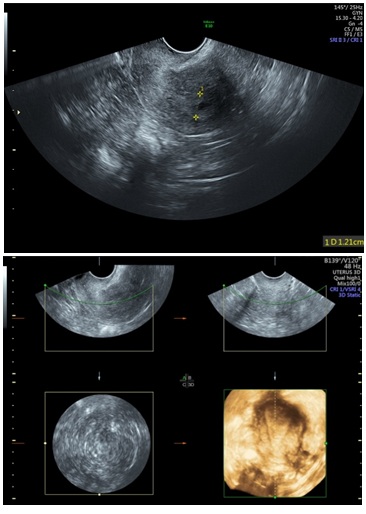

Figure 5: 2D & 3D USG showing Polyp in Uterine Cavity.

Figure 9: D & 3D USG showing Endometium Hyperplasia with small cystic space.

Three-Dimensional Ultrasonography (3D USG) in comparison to hysteroscopy is less invasive, cheaper, easily accepted by most patients and does not require much training. In most cases an endometrial polyp can be differentiated from the submucous fibroid based on the imaging characteristics. The polyps are typically round in shape, smooth in outline, and are generally echogenic, compared to the endometrium or are isoechoic to it. The underlying endometrial-myometrial interface is preserved (Figure 5). Moreover the presence of a vascular pedicle has a positive predictive value of up to 81.3%. Fibroids are more inhomogeneous, hypoechoic, and there is a loss of endometrial-myometrial interface. The percentage of the intra cavitary portions of the submucous fibroids i.e., grade of submucous myoma can be assessed on 3D USG by the degree of distortion caused by it (Picture 6).

A study by Van den Bosch [9] evaluated diagnostic accuracy of 3DTVS in detection of uterine cavity lesion in women with abnormal uterine bleeding. They found endometrial polyp in 26%, submucous myoma in 7%, endometrial hyperplasia in 6%, and cancer in 1% of subjects. They also reported 93% diagnostic accuracy, 96% sensitivity, and 91% specificity. In our study, 3D-TVS detected all cases of submucous myoma while missed 13 cases out of twenty eight cases with endometrial polyps. Even though there were only a small number of cases with submucous myoma, 3D TVS demonstrated 100% diagnostic accuracy. Hence hysteroscopy is recommended for accurate detection and diagnosis of uterine cavity lesion.